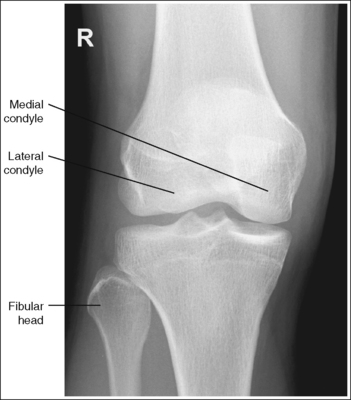

The knee demonstrates an AP projection. The medial and lateral femoral epicondyles are in profile, the femoral condyles are symmetrical, the intercondylar eminence is centered within the intercondylar fossa, and the tibia is superimposed over 0.25 inch (0.6 cm) of the fibular head.

• To obtain an AP knee projection, place the patient in a supine position with the knee fully extended. Internally rotate the leg until an imaginary line drawn between the medial and lateral femoral epicondyles is positioned parallel with the IR (Figure 6-71). This positioning places the medial and lateral femoral epicondyles at equal distances from the IR as well as medially and laterally in profile, respectively. It also centers the intercondylar eminence within the intercondylar fossa and draws the fibular neck and a portion of the fibular head from beneath the tibia.

• Effect of rotation. If the femoral epicondyles are not positioned parallel with the IR, an AP projection has not been obtained. If the patient's leg was not internally rotated enough to place the epicondyles at equal distances from the IR, they are not in profile, the medial femoral condyle appears larger than the lateral condyle, and the tibia is superimposed over more than 0.25 inch (0.6 cm) of the fibular head (see Image 54). If the patient's leg was internally rotated more than needed to place the femoral epicondyles at equal distances from the IR, the epicondyles are not demonstrated in profile, the lateral femoral condyle appears larger than the medial condyle, and the tibia is superimposed over less than 0.25 inch (0.6 cm) of the fibular head (see Image 55).

The knee joint space is open, the anterior and posterior condylar margins of the tibia are superimposed, the intercondylar eminence and tubercles are demonstrated in profile, and the fibular head is demonstrated approximately 0.5 inch (1.25 cm) distal to the tibial plateau.

• The anterior and posterior condylar margins of the tibia are superimposed if the correct central ray angulation, as determined by the patient's upper thigh and buttocks thickness, is used. By studying the tibial plateau region, you will see that the tibial plateau slopes distally approximately 5 degrees from the anterior condylar margin to the posterior condylar margin on both the medial and lateral aspects (Figure 6-72). Only if the central ray is aligned parallel with the tibial plateau slope is an open knee joint space obtained.

• Determining the central ray angulation. When a patient is placed in a supine position, the degree and direction of the central ray angulation required depend on the thickness of the patient's upper thigh and buttocks. This thickness determines how the lower leg and the tibial plateau align with the IR. Figure 6-73 shows a guideline that can be used to determine the central ray angulation for different body sizes; it illustrates the relationship of the tibial plateau to the imaging table as the patient's upper thigh thickness increases. Note that a decrease occurs in femoral decline, and a shift occurs in the direction of the tibial plateau slope as the thickness of the thigh decreases. Because of this plateau shift, the central ray angulation must also be adjusted to keep it parallel with the plateau and to achieve an open knee joint. For optimal AP knee projections, measure from the patient's anterior superior iliac spine (ASIS) to the imaging table on either side to determine the central ray angulation to use for each knee examination. When measuring this distance, do not include the patient's abdominal tissue. Keep the calipers situated laterally next to the ASIS. If the measurement is less than 18 cm, a 5-degree caudal angle should be used. If the measurement is 19 to 24 cm, a perpendicular beam should be used. If the measurement is greater than 24 cm, a 5-degree cephalad angle should be used. Using the correct central ray angulation not only results in an open knee joint space but also provides optimal demonstration of the intercondylar eminence and tubercles without foreshortening.

• Analysis of joint space narrowing. On an AP knee projection with adequate positioning, joint space narrowing is evaluated by measuring the medial and lateral aspects of the knee joint, which are also referred to as compartments. The measurement of each of these compartments is obtained by determining the distance between the most distal femoral condylar surface and the posterior condylar margin of the tibia on each side. Comparison of these measurements with each other, with measurements from previous images, or with measurements of the other knee determines joint space narrowing or a valgus or varus deformity. In a valgus deformity the lateral compartment is narrower than the medial compartment; in a varus deformity the medial compartment is narrower (see Images 56 and 57). Precise measurements of the compartments are necessary to ensure early detection of joint space narrowing and are best obtained when the knee joint space is completely open. If an inaccurate central ray angulation was used for an AP knee projection, the knee joint is narrowed or obscured, the intercondylar eminence and tubercles are foreshortened, and the tibial plateau is demonstrated.